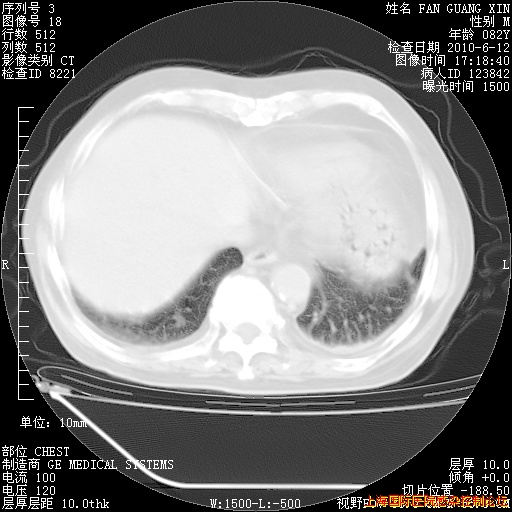

今天复查CT

今天CT

整整相隔30天的肺部CT好像有所好转啊。甲强龙减量第3天,需要观察体温。

海管,自昨日你和我通完话后,不知您岳父消化道症状有无缓解?体温怎样?阅读7.12日胸部ct,个人认为目前激素治疗是有效的,甲强龙减量是适宜的。因在抗痨治疗,需密切观察肝功、肾功能和血常规。不过,老年、长期住院和大量使用激素,很担心菌群失调发生